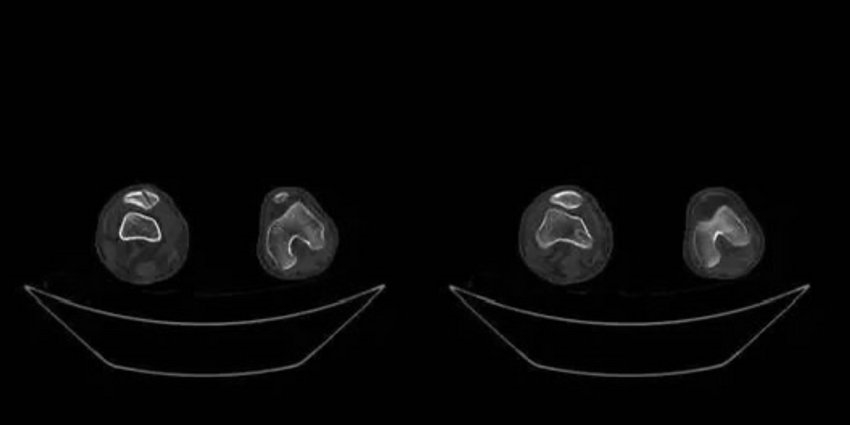

管床医师张鹏飞任耐心细致的讲解病情,患者同意行内侧副韧带重建术,术前却顾虑术后伤口留疤、康复困难等。经科主任徐明杰的耐心开导,患者最终下定决心行手术治疗。手术由徐明杰主任主刀,顺利完成了关节镜下内侧副韧带重建+半月板成形术(见图2、图3)。术后切口愈合良好,术后仅4天即出院。出院后,张鹏飞主治医师及时随访,并通过微信指导患者行康复锻炼,取得良好的效果(见图4)。

图2 术后复查CT